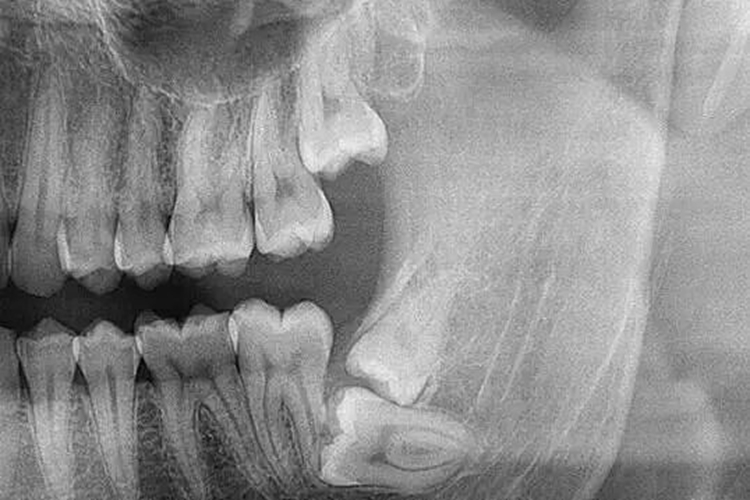

X线牙片显示出牙的外轮廓白色的影像,代表牙冠部分釉质,牙髓腔呈黑色透明影像,根管口至根尖孔呈逐渐变细的黑色透明影像。

X线牙片可发现牙体牙周病变,如龋齿患者,可通过X线牙片了解龋坏程度、范围,以及龋洞和牙髓腔之间的关系,还可检查填充材料下有无继发性龋坏。另外,根尖周炎症、牙周炎症、埋伏牙、阻生牙等均可通过X线牙片诊断。